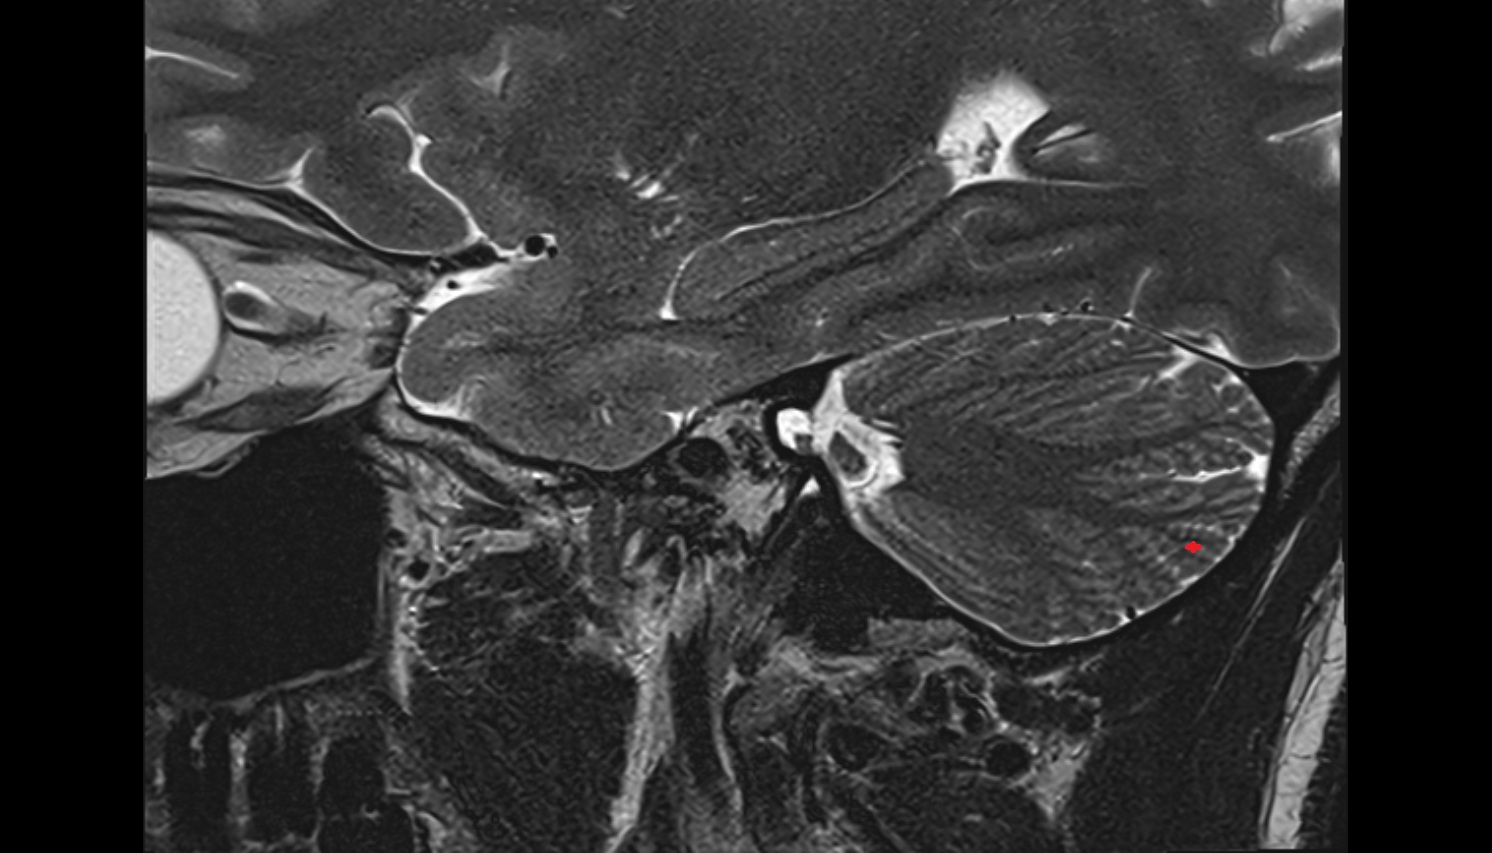

- Temporomandibular joint

- Mandibular condyle

- Mandibular fossa

- Articular disc of temporomandibular joint

- Articular eminence

- Superior head of lateral pterygoid muscle

- Inferior head of lateral pterygoid muscle